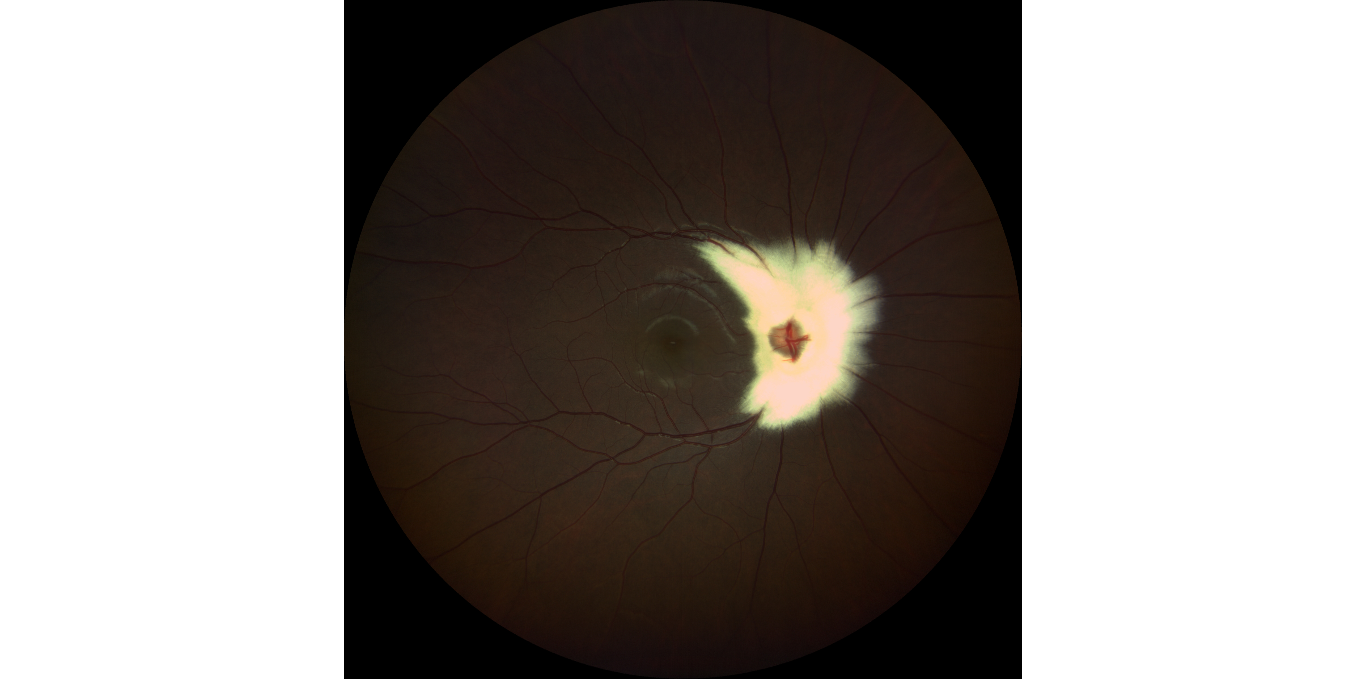

BEST DISEASE WITH RETINAL HAEMORRHAGE IN FLOWER PETAL PATTERN

Author: Dr. SWATHY HARIDAS